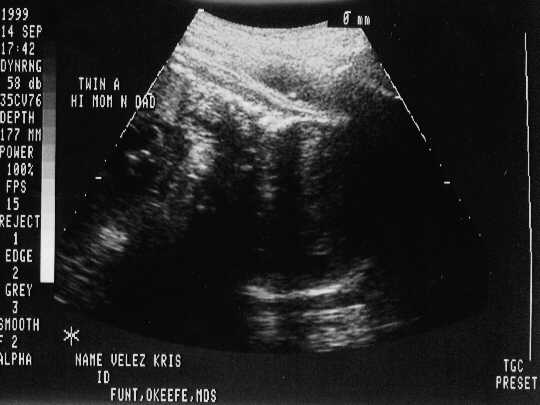

September 14, 1999 Sonograms

Kris is in her 35th week. She can go in labor anytime now!

Patrick Joseph weighs 5.2 pounds.

Patrick Joseph

sono-0914-a.JPG - 20.5 K